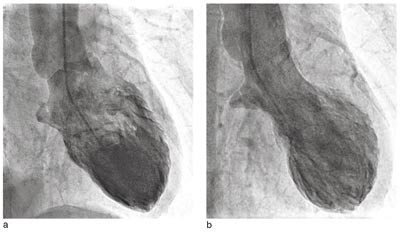

Pasient 3. 76 år gammel kvinne, som gjennom mange år hadde fått substitusjonsbehandling for hypotyreose. Ellers hadde hun stort sett vært frisk. Etter å ha deltatt i seniordans følte hun seg sliten og fikk ikke sove på grunn av smerter i venstre skulder. Morgenen etter hadde hun fortsatt smerter i skulderen og også i venstre side av thorax. Vel et halvt døgn etter smertedebut ble hun innlagt i sykehus. Hun var ved innleggelsen smertefri, og det var ingen kardiopulmonale svikttegn. Arterielt blodtrykk var 120/85 mm Hg, pulsfrekvensen 64 per minutt. Temperaturen ble målt til 38,1 °C. Ved auskultasjon fant man en systolisk bilyd grad III over prekordiet, ellers var det ingen vesentlige funn ved organstatus. EKG ved innkomst viste sinusrytme og lett ST-elevasjon i avledningene I, II og V₂ – V₆. Dagen etter innkomst var det noe mer tydelig ST-elevasjon i II, III og AVF, men i V₂ – V6 så man dype, negative og symmetriske T-takker uten ST-elevasjon. Det tilkom ingen Q-takker. Senere var det fullstendig normalisering av EKG (fig 2). Ekkokardiografi innkomstdagen viste akinesi av apex cordis og apikale tredel av venstre ventrikkel (fig 3a, 3b). Det var tydelig systolisk anterior bevegelse («SAM») av fremre mitralklaff, med betydelig trykkgradient i venstre ventrikkels utløpstrakt, målt til 45 mm Hg med doppler (fig 3e). Det var lettgradig mitralklaffinsuffisiens. Kontrollundersøkelse neste dag viste ingen vesentlig endring, men kontrollekkokardiografi fem dager etter innkomst viste tilnærmet full normalisering av venstre ventrikkels kontraktilitet (fig 3c, 3d). Trykkgradienten i venstre ventrikkels utløpstrakt var redusert til 20 mm Hg.

Hun fikk etter innkomst behandling med betablokker, acetylsalisylsyre og klopidogrel. Under hele oppholdet var hun symptomfri, og forløpet var ukomplisert. Ni dager etter innkomst ble det utført koronarangiografi, som viste normale koronararterier. Laboratorieprøvene viste maksimal troponin T-verdi på 0,34 µg/l, som ble målt ved innkomst. Bortsett fra en CRP på 74 mg/l var laboratorieprøvene normale. Revmatoid faktor var negativ og antinukleære antistoffer svak positiv, med alle undergrupper negative. Kvinnen har senere vært symptomfri, og kontrollundersøkelse åtte måneder etter innleggelsen viste fortsatt helt normal venstre ventrikkel-funksjon, uten tegn til obstruksjon i venstre ventrikkels utløpstrakt. Hun brukte da ingen hjertemedisiner.

Hos mange av pasientene med transitorisk apikal ballonering av venstre ventrikkel er det observert obstruksjon i ventrikkelens utløpstrakt (2, 13), noe vi også observerte hos en av våre pasienter (fig 3). Det antas at noen pasienter ut fra hjertets anatomi og geometri er predisponert for obstruksjon i venstre ventrikkel, og at dette manifesteres ved kraftig adrenerg stimulasjon (13). Et prominerende basalt interventrikulærseptum, sammen med redusert venstre ventrikkel-volum, kan være årsaken til at kvinner er predisponert for obstruksjon i venstre ventrikkels utløpstrakt. Obstruksjon med trykkgradient i ventrikkelens utløpstrakt kan gi betydelig trykkøkning i apikale del av ventrikkelen, og dette kan være en del av forklaringen på hvorfor alltid apikale segmenter av venstre ventrikkel er akinetiske ved dette syndromet (7). Det finnes imidlertid flere andre forklaringer, blant annet at venstre ventrikkels apeks ikke har trelags myokardstruktur, og at apeks er grensesonen mellom perfusjonsområdene til de store koronararteriene (2).